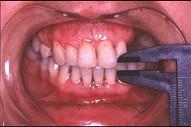

关于颞下颌关节强直(如图)的描述哪项是正确的 ( )

关于颞下颌关节强直(如图)的描述哪项是正确的 ( )![]()

A颞下颌关节外强直是关节外纤维黏连

B颞下颌关节内强直是关节内骨性黏连

C混合性下关节强直是指关节内,外强直同时发生,又称颌间挛缩

D关节及关节周围组织器质性病变造成开口困难或完全不能开口

E颞下颌关节强直常常突然发生